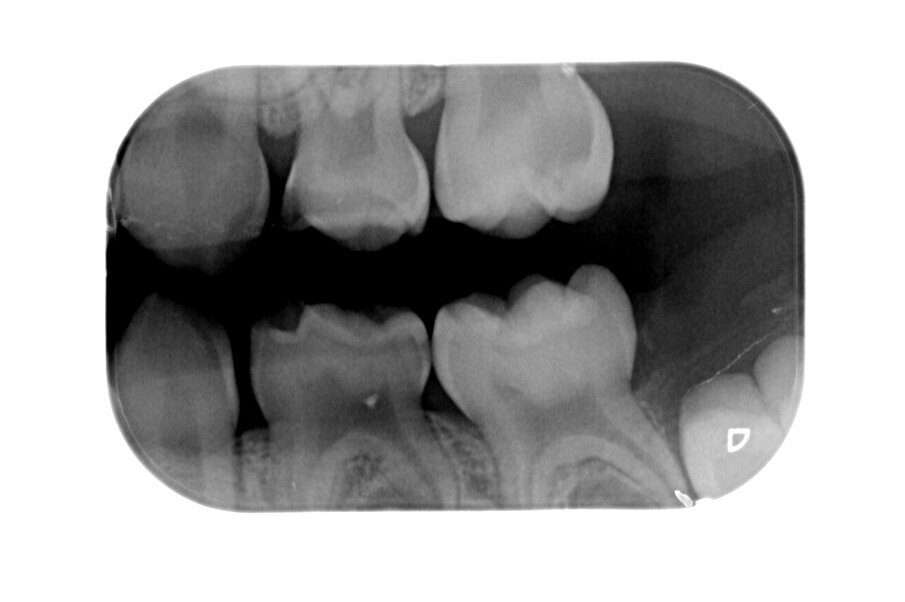

Afbeelding 7. Casus 3: 13-02-19. Intraorale foto 55 bij 3-jarig kind met zuigflescariës.

Afbeelding 8. Casus 3: 13-02-19. Intraorale foto 65 bij 3-jarig kind met zuigflescariës.

Afbeelding 9. Casus 3: 18-10-19. BWR, zie 55.

Afbeelding 10. Casus 3: 18-10-19. BWL, zie 65.